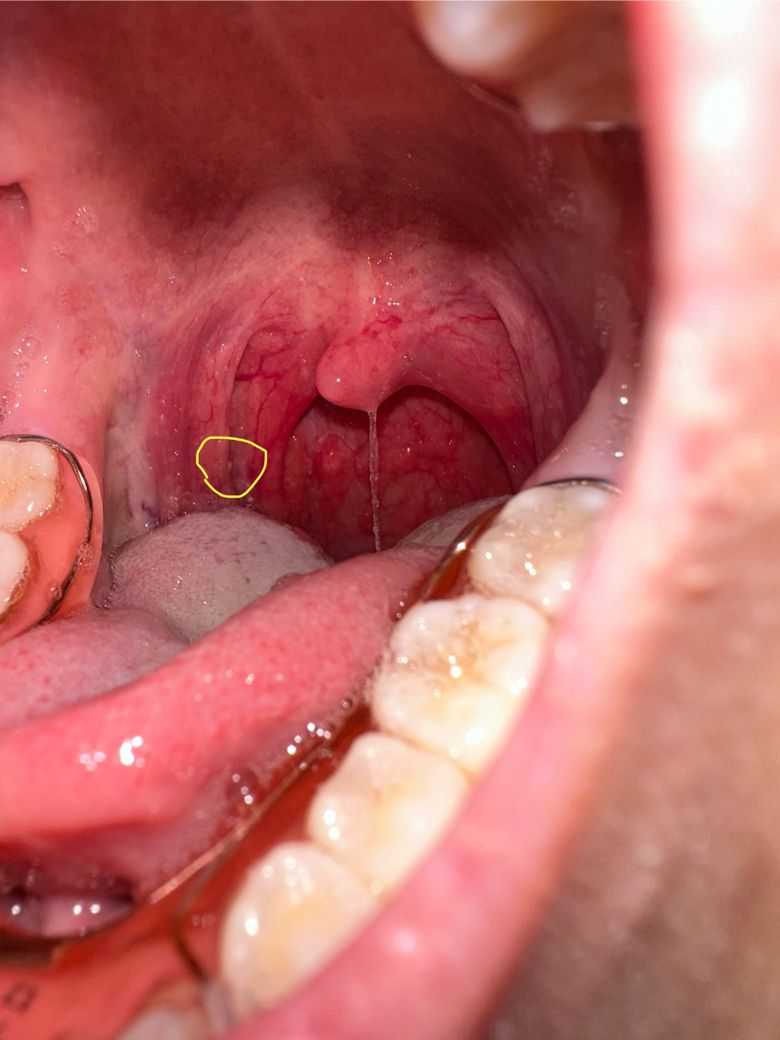

어제는 오른쪽부터 아파서 구내염인줄알고 프로폴리스 사탕이랑 비타민약을 먹었습니다. 그래서 괜찮을줄알았는데 아침에 일어나니 전체적으로 아프고 침삼길때마다 아픕니다ㅠ 혹시 작긴하지만 표시한 부분이 구내염인가요? 육안으로 봤을때는 하얀 알갱이 느낌입니다 하얀 가래도 계속 생깁니다ㅠ

구내염 같아 보이지는 않고, 전반적으로 붉게 보이는 양상을 고려하면 인후염이라고 볼 수 있지요. 소염 진통제를 드셔 보셔도 도움이 될 수 있습니다.